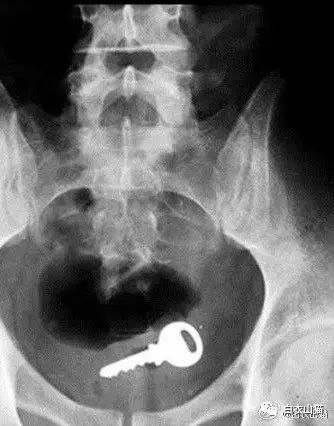

芝麻开门

塞了钥匙进去,难道是要叫肛门芝麻开门?